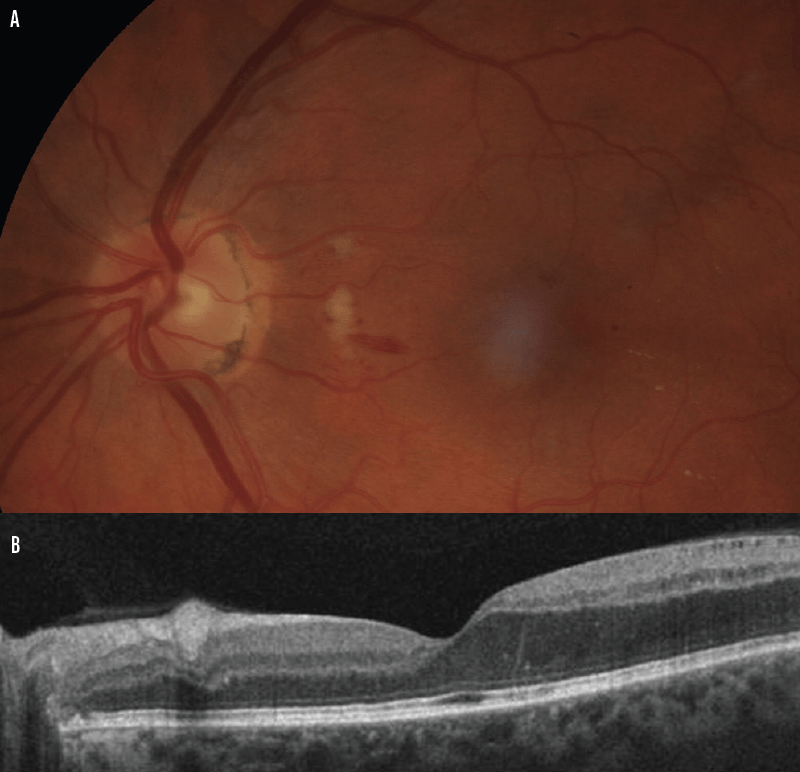

Multiple cotton wool spots in a patient with HIV retinopathy (arrows

Multiple peripapillary cotton wool spots in both eyes at presentation Cotton Wool Spots Retina Symptoms Retinal vasculitis is used as a descriptive term to explain a conglomerate of typical clinical manifestations including perivascular. While the spots themselves don’t. Cotton wool spots are small areas of damage on the retina. Cotton wool spots (cws) are fluffy white or yellow spots that can appear on the retina. Narrowing of tiny blood vessels. Thickening of the arterioles’ walls.. Cotton Wool Spots Retina Symptoms.

Cotton Wool Spot Oct Cotton Wool Spots Retina Symptoms While the spots themselves don’t. Narrowing of tiny blood vessels. Although they tend not to have any. The most common symptoms associated with retinal cws can include scotoma, arcuate defects, blurred vision, and amaurosis fugax. These spots signify local ischemia, where blood flow to the retinal nerve fibers is reduced or obstructed, leading to their swelling and eventual necrosis. Cotton. Cotton Wool Spots Retina Symptoms.